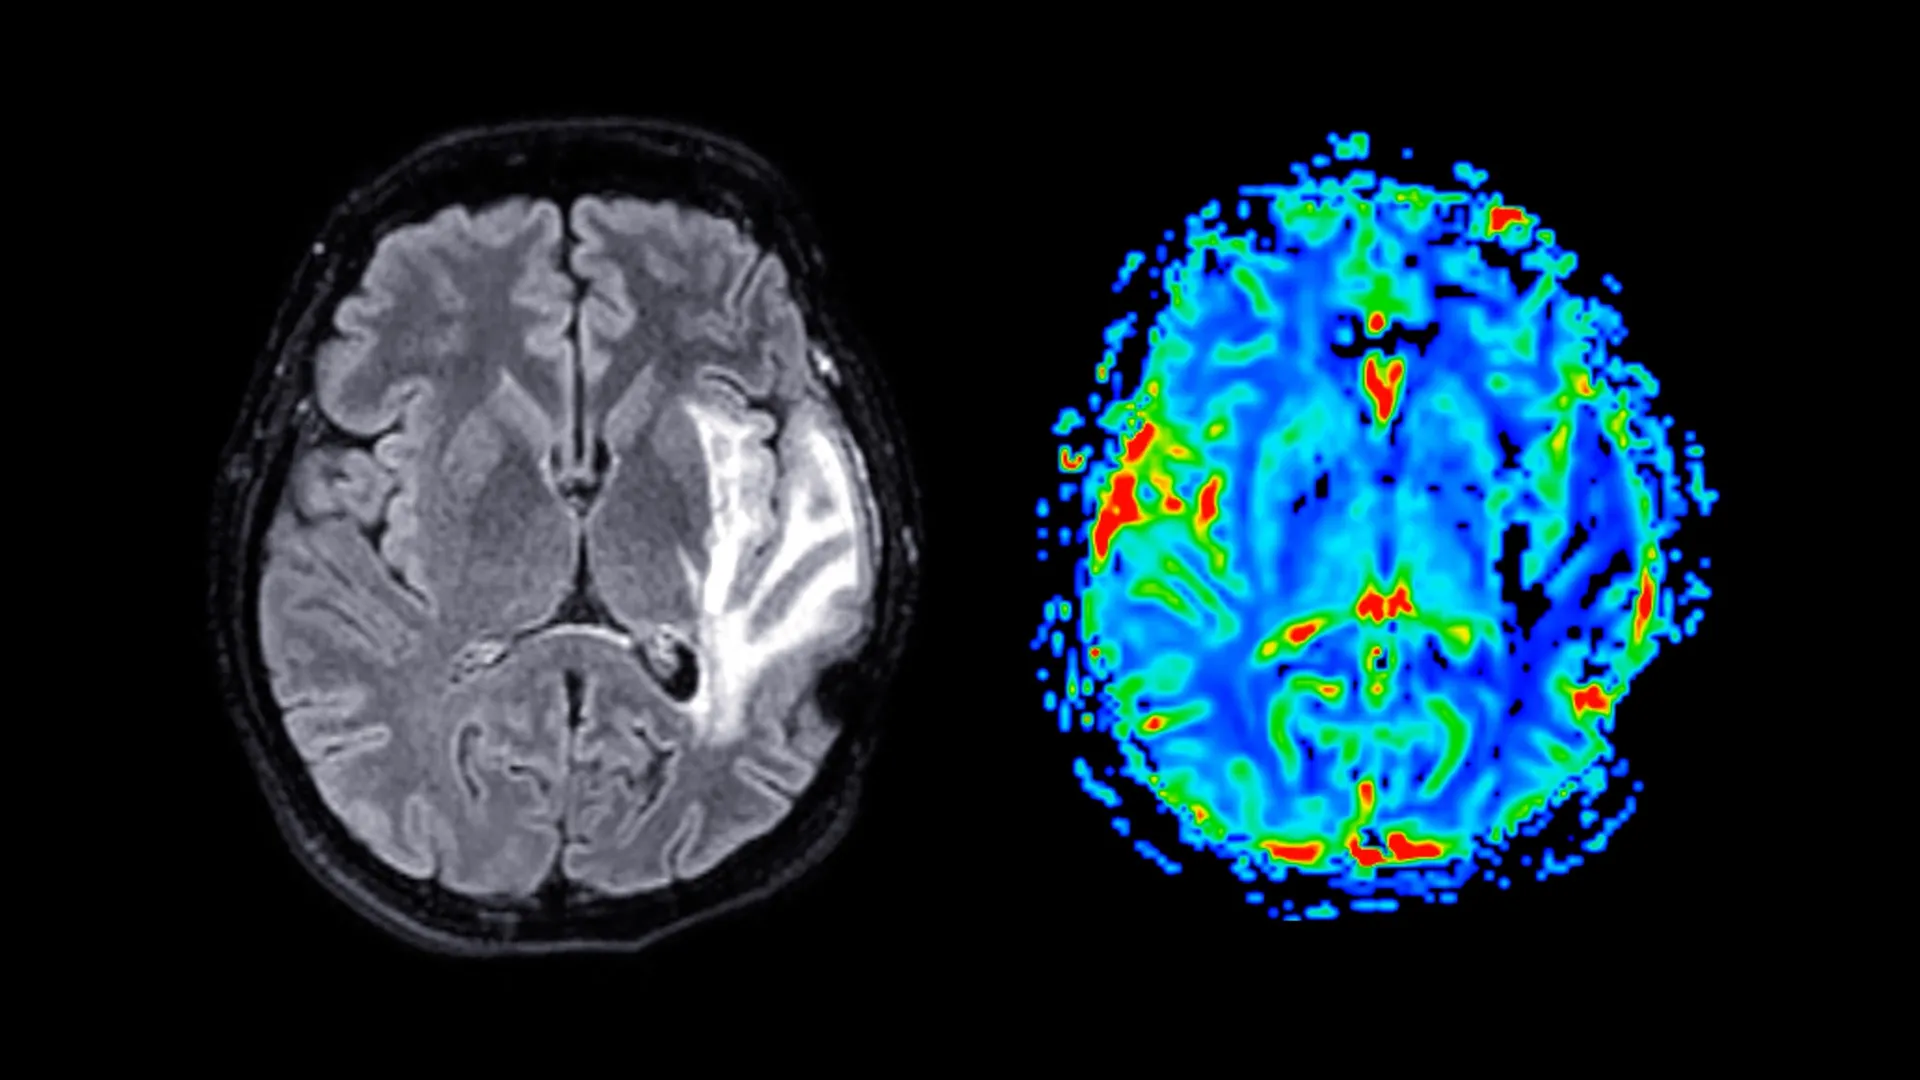

In an endeavor to foster a more profound understanding of these complex interactions, the research team meticulously analyzed a substantial dataset drawn from the UK Biobank, encompassing the participation of nearly 125,000 women. The cohort was strategically categorized into three distinct groups: premenopausal women, postmenopausal women who had never undergone HRT, and postmenopausal women who had received HRT. Participants meticulously completed a battery of questionnaires designed to assess various facets of their health, including the subjective experience of menopausal symptoms, their mental health status, established sleep patterns, and general health indicators. A subset of these participants also undertook standardized cognitive assessments to evaluate memory function and reaction times. Furthermore, approximately 11,000 women underwent advanced magnetic resonance imaging (MRI) scans, providing researchers with an invaluable opportunity to scrutinize structural differences within the brain. The average age at which participants experienced menopause was approximately 49.5 years, with those prescribed HRT typically initiating treatment around the age of 49.

The neuroimaging data revealed a significant reduction in grey matter volume among postmenopausal women, a phenomenon observed irrespective of their HRT utilization. Grey matter, the brain’s primary locus for processing information, orchestrating motor control, and underpinning memory formation and emotional regulation, plays a pivotal role in numerous cognitive functions. The regions exhibiting the most pronounced volumetric changes included the hippocampus, a brain structure critically involved in the consolidation and retrieval of memories; the entorhinal cortex, which serves as a crucial gateway for information transfer between the hippocampus and other cortical areas; and the anterior cingulate cortex, a key component of the brain’s executive functions, instrumental in emotion regulation, decision-making, and attentional control.

These observed neurological alterations may hold significant implications for understanding women’s long-term brain health, particularly concerning their predisposition to neurodegenerative diseases. Professor Barbara Sahakian, the senior author of the study from the Department of Psychiatry, pointed out that the brain regions identified as showing these differences are notably those typically affected by Alzheimer’s disease. She suggested that menopause could potentially render these women more vulnerable to such conditions later in life. While acknowledging that menopause is not the sole determinant, she posited that these findings might contribute to explaining the observed disparity in dementia prevalence, where women are diagnosed with the condition at nearly twice the rate of men.